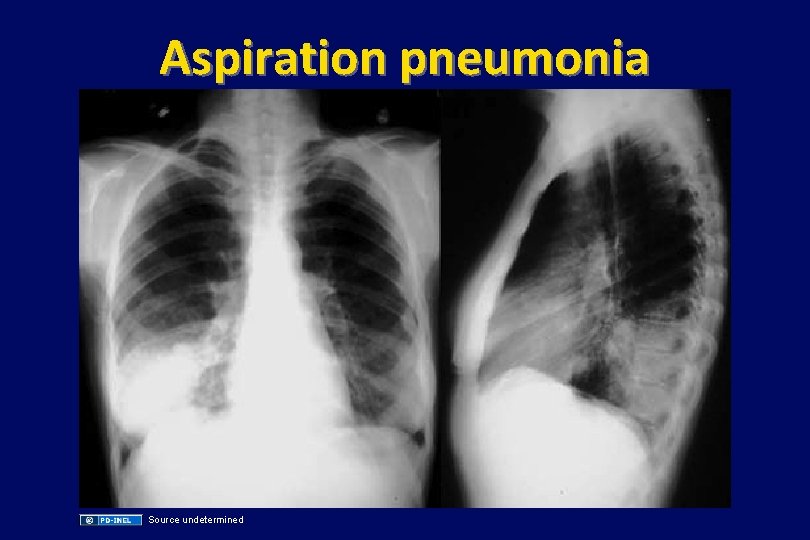

Case (continued) • He is admitted and started on ceftriaxone for probably pneumonia • Later the same night, the patient starts coughing copious amounts of grayish, putrid sputum that can be detected on the next ward. • A chest xray is taken, and treatment with metronidazole is added.

Aspiration pneumonia Source undetermined

Oral, Gram-negative anaerobes • Common pathogens in dental infections, chronic sinusitis, aspiration pneumonia, lung abscesses – Porphyromonas asaccharolytica, gingivalis, forsythus – Prevotella melaninogenicus (named for brown pigment production) • These species are usually (not always) sensitive to clindamycin. PCN+metronidazole usually works well. • Infections are polymicrobial and usually include oral (viridans) streptococci, anaerobic strep, and other oral bacteria.